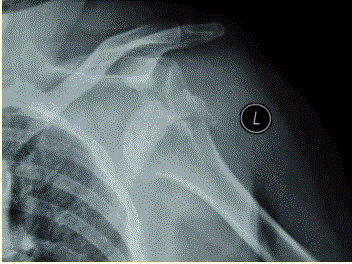

问题 患者女,58岁,左肩关节外伤,医院就诊,行X线检查,如下图。 这种情况损伤的概率最高的神经是

选项 A、尺神经 B、肌皮神经 C、正中神经 D、肩胛上神经 E、桡神经 F、腋神经

答案 F